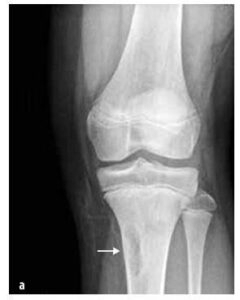

Benigne tumore

Ovi se tumori javljaju češće u djece nego maligni tumori, npr. koštani tumori (osteoidni osteom, osteoblastom, eozinofilni granulom), tumori vezivnog tkiva (fibromatozna displazija, neosifikirajući fibrom (vidi Sliku 7)), koštane ciste, tumori hrskavice (osteohondrom, enohondrom, hondroblastom).

Slika br. 7

Neosteogenni koštani fibrom